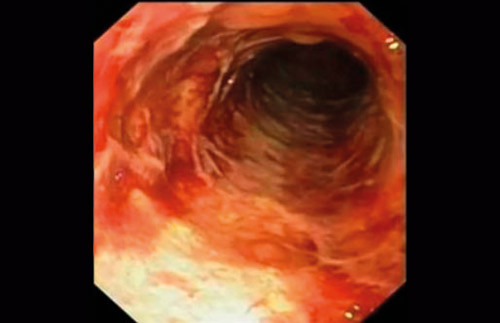

Lang aplasitid ble påvist hos dem som trengte kirurgisk behandling. Kortvarig aplasi begrenser inflammasjonen til tarmmucosa (mukositt), langvarig aplasi forårsaker kontinuerlig bakteriell invasjon av tarmveggen, med ulcerasjoner (fig 2), nekrose og perforasjon. Disse funnene er i samsvar med observasjoner gjort av Wade & Nava (8). Imidlertid forekommer økt fortykkelse av tarmveggen også ved kolitt utløst av Clostridium difficile, transplantat-mot-vert-sykdom, cytomegalovirusinfeksjon og tarmiskemi (4). Derfor må disse tilstandene utelukkes hvis radiologiske funn skal ligge til grunn for diagnosen nøytropen enterokolitt.